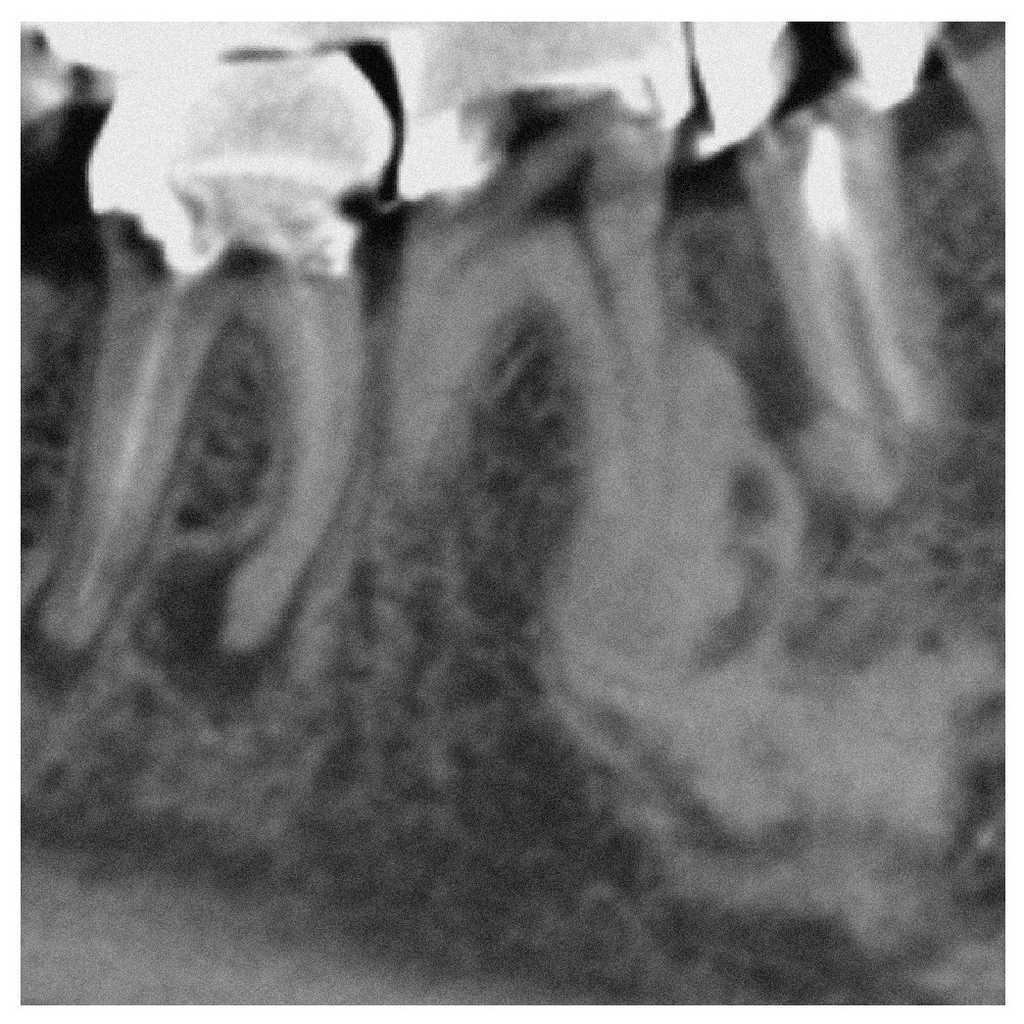

En el plano axial de la TVD se observa una masa hiperdensa y homogénea que ocupa casi toda la anchura de la porción alveolar. Dicha masa está rodeada por un borde hipodenso (figs. 2 y 3). En el plano vertical, se constata que la masa no está en contacto con el conducto dentario inferior del lado derecho (fig. 4).

Figura 3. Tomografía volumétrica digital dental: plano coronal.